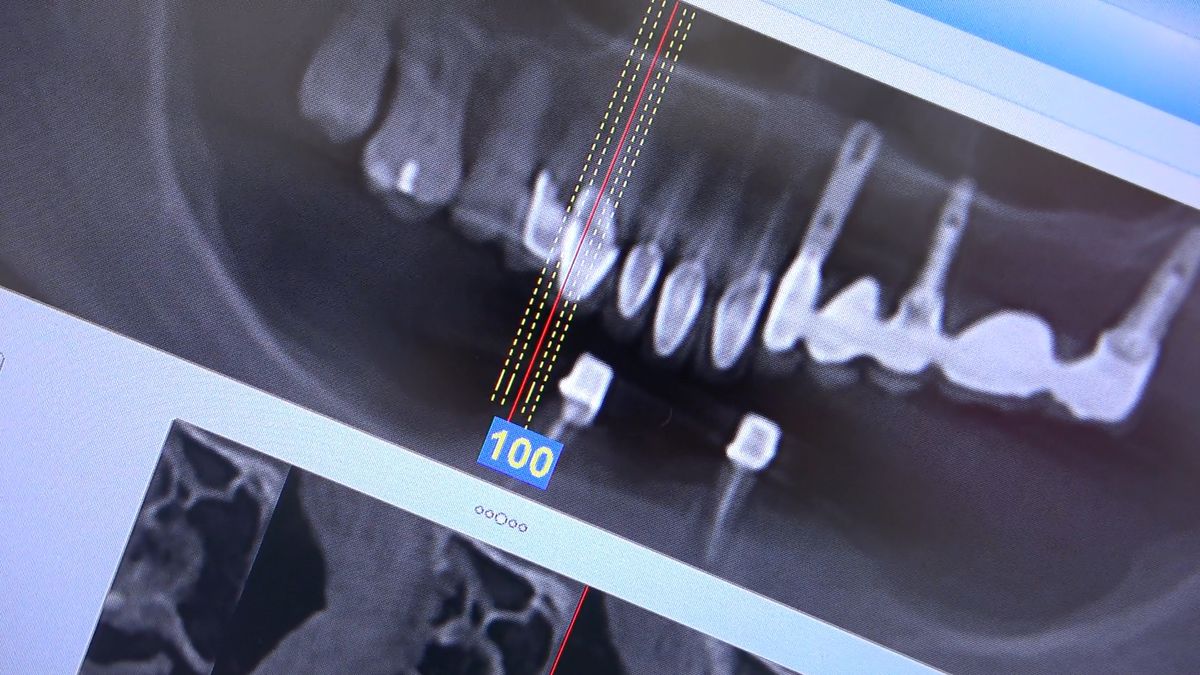

Practiculum Implantologii – Sezon VIIB, sesja 7, dzień 2